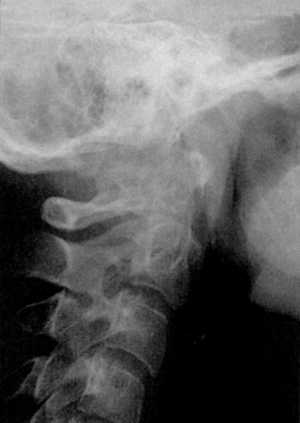

Диагностика. Рентгенография верхнего шейного отдела позвоночника в боковой

проекции выявляет расширение суставной щели Крювелье. В норме расстояние между

задней поверхностью передней дуги атланта и передней поверхностью зубовидного

отростка аксиса равняется: в положении сгибания -1,8 мм, разгибания - 2,2 мм,

в нейтральном положении - не более 2 мм (Hinck, Hopkins, 1960).

КТ и цифровая спондилография - важные методы диагностики вывихов атланта (рис.

1.7 и 1.8). МРТ позволяет определить не только дислокацию атланта, но и степень

компрессии спинного мозга (рис. 1.9).

Рис 1.7. Ротационный вывих атланта по

данным цифровой спондилографии |

Рис. 1.8. Вывих в атланто-аксиальном сочленении по данным

цифровой спондилографии |